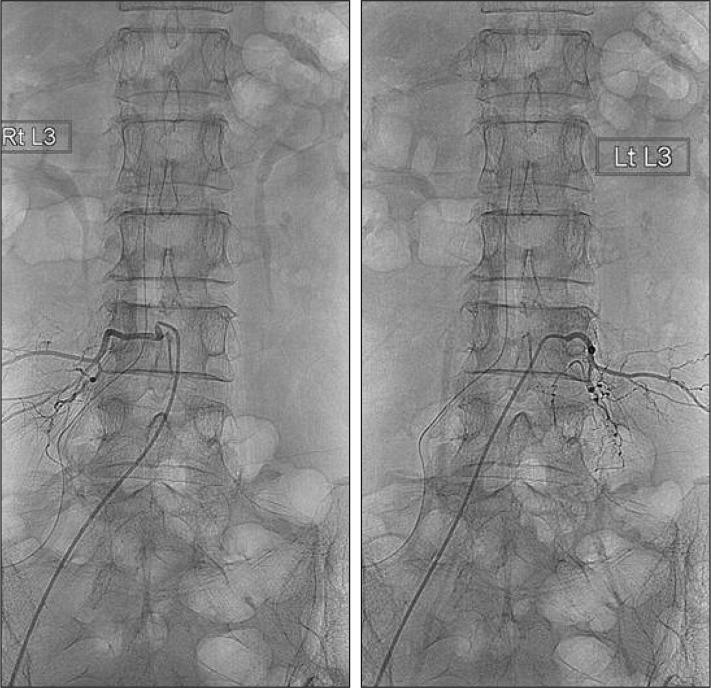

Spinal epidural arteriovenous hemangioma mimicking lumbar disc herniation.

A spinal epidural hemangioma is rare. In this case, a 51 year-old female patient had low back pain and right thigh numbness. She was initially misdiagnosed as having a ruptured disc with possible sequestration of granulation tissue formation due to the limited number of spinal epidural hemangiomas and little-known radiological findings. Because there are no effective diagnostic tools to verify the hemangioma, more effort should be put into preoperative imaging tests to avoid misdiagnosis and poor decisions).